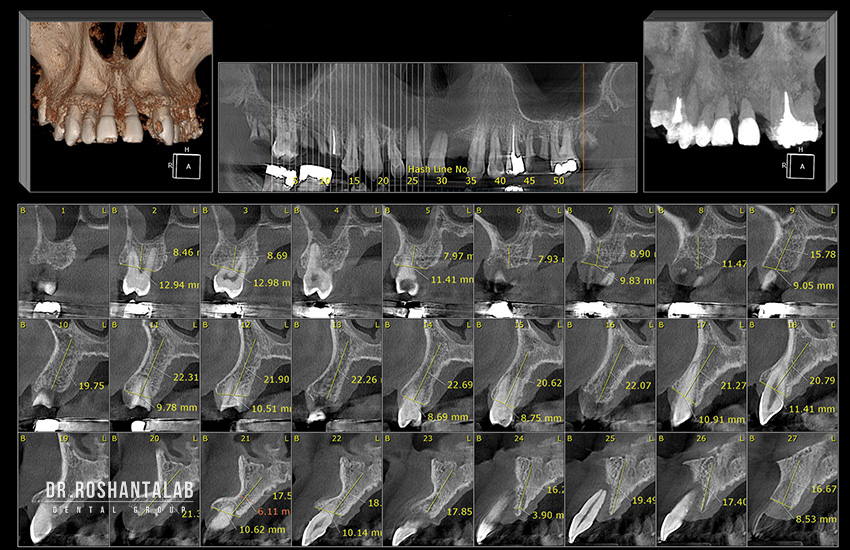

ایمپلنت دیجیتال یک روش انقلابی و مدرن در حوزه کاشت دندان است که تمام مراحل برنامهریزی، طراحی و اجرای جراحی را با استفاده از فناوریهای پیشرفته دیجیتال انجام میدهد. این روش از ابزارهایی مانند تصویربرداری سهبعدی CBCT (Cone Beam Computed Tomography)، نرمافزارهای طراحی کامپیوتری CAD/CAM، اسکنرهای داخل دهانی، چاپگرهای سهبعدی و راهنماهای جراحی دیجیتال بهره میبرد. برخلاف ایمپلنتهای سنتی که عمدتاً بر اساس عکسهای دوبعدی رادیوگرافی و تجربه دستی جراح انجام میشدند، ایمپلنت دیجیتال کل فرآیند را به صورت کاملاً خودکار، قابل پیشبینی و با دقت بسیار بالا مدیریت میکند.

این مرحله با یک جلسه مشاوره آغاز میشود که در آن دکتر روشنطلب یا یکی از متخصصان تیم، تاریخچه پزشکی کامل بیمار را بررسی میکند. این شامل سؤال درباره بیماریهای زمینهای مثل دیابت، فشار خون، بیماریهای خودایمنی، مصرف داروهای خاص (مثل بیسفسفوناتها)، عادات مانند سیگار کشیدن و حتی سطح استرس بیمار است. سپس، اسکن CBCT انجام میشود که در عرض ۱۰ تا ۱۵ ثانیه، تصاویری سهبعدی با رزولوشن بسیار بالا از فک بالا، فک پایین، موقعیت دقیق عصبهای دندانی، سینوسهای فکی و تراکم استخوان در هر ناحیه ارائه میدهد. این اسکن اطلاعاتی معادل صدها عکس رادیوگرافی دوبعدی فراهم میکند و به جراح اجازه میدهد تا بهترین استراتژی را انتخاب کند. در گروه دندانپزشکی دکتر روشنطلب، نتایج اسکن بلافاصله در نرمافزارهای پیشرفته CAD/CAM بارگذاری میشود تا شبیهسازی سهبعدی از نتیجه نهایی لبخند ایجاد شود و بیمار بتواند آن را ببیند و تأیید کند. - برنامهریزی کامپیوتری دقیق و طراحی راهنمای جراحی: